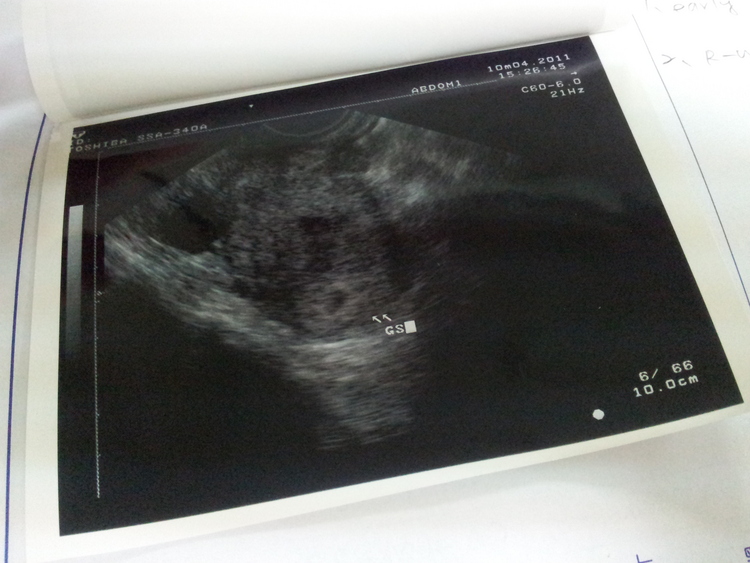

胚胎在子宮內了,但是好像偏低耶!!!

最後一次MC是8/23,今天去醫院照胚胎確認著床…

但醫生說著床位置比較低, 安排我下禮拜再去檢查看看??

雖然很開心順利在子宮著床了

但是看到照片感覺好膽心哦!!

胚胎不是要在中間一點才對嗎?

我的好像有點低耶~~~

胚胎很清楚的在子宮內,有點偏左的地方,